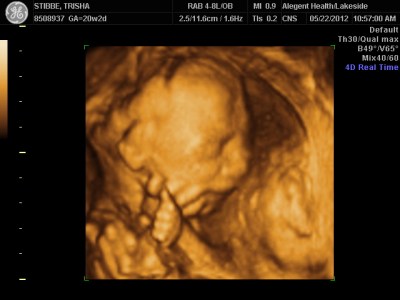

Ultrasound Day!